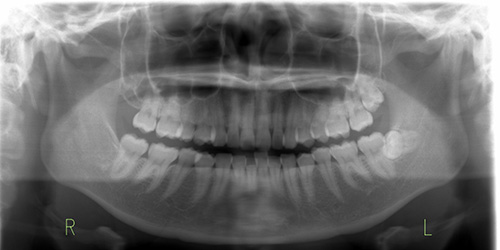

患者様のお口の状態や歯並び、かみ合わせなどを確認させていただき、エックス線撮影やお口の中とお顔の写真撮影、型取りを行っていきます。

検査結果と分析をもとに診断し、カウンセリングでお伺いした内容に基づいて治療計画を立案いたします。診断結果や治療の流れなどについて詳しく丁寧にご説明いたします。